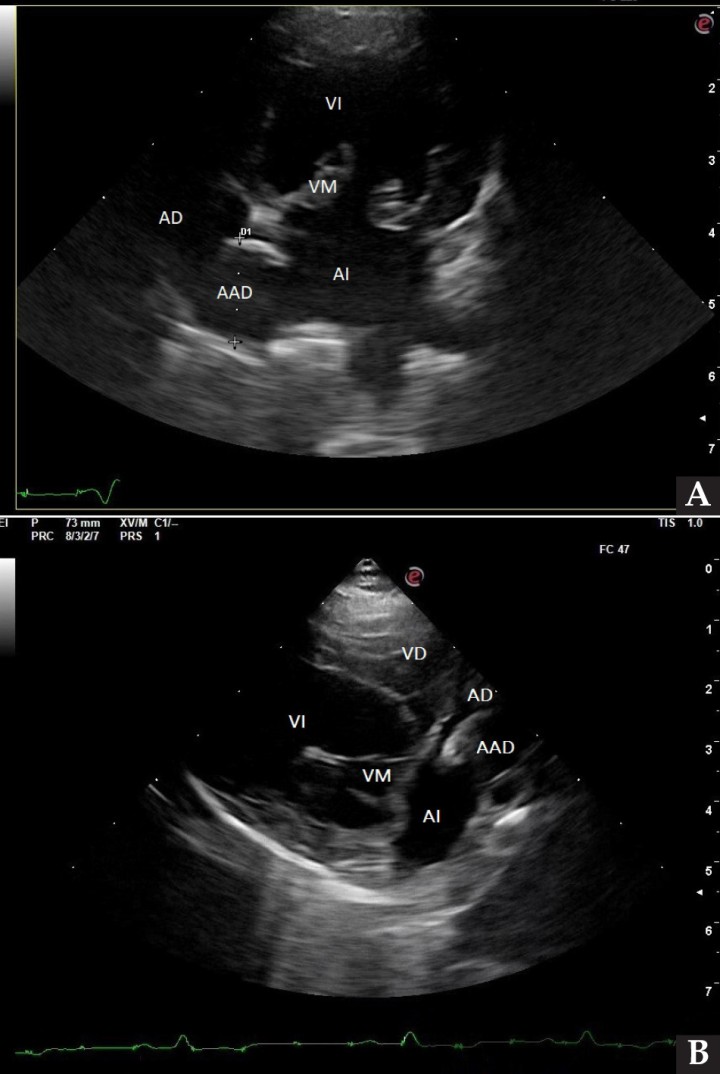

Se realizó una angio-TC de la cavidad torácica para caracterizar la masa mediastínica craneoventral. El estudio se realizó bajo anestesia general y con la paciente en decúbito esternal. Se realizaron series pre-contraste y post-contraste, inmediatamente y a los 3 minutos tras la administración de un contraste iodado hidrosoluble no iónico (iopromida 300 mg I/ml a una dosis de 600 mg I/kg intravenoso, administrado de forma manual) con cortes de 3 mm de grosor e intervalo 1,5 mm con algoritmo estándar (tejido blando) y pulmón. El estudio de TC se evaluó en ventana de tejido blando, hueso y pulmón, visualizándose en el área craneal al atrio derecho una estructura redondeada y bien definida (22UH) de medidas aproximadas 1,95 cm DV x 1,87 CrCd x 2,5 cm LL (Figs. 4 y 5). Tras la administración de contraste, esta estructura se llenó rápidamente de contraste de forma homogénea, observándose una comunicación con el atrio derecho, midiendo el área de la comunicación 1,43 cm. El diagnóstico presuntivo fue de un aneurisma de la aurícula derecha.

<p>Imágenes de Tomografía Computarizada. Inmediatamente tras la administración de contraste (<strong>A</strong>) en ventana de tejido blando. Se observa una estructura quística en la zona craneal del atrio derecho y que contacta con la aurícula derecha, rellenándose de contraste inmediatamente tras su administración (flechas blancas). (<strong>B</strong>) Imagen reconstruida en volumen rendering, donde se visualiza el aumento de tamaño de la aurícula derecha (flecha blanca).</p>

Figura 5

Imágenes de Tomografía Computarizada. Inmediatamente tras la administración de contraste (A) en ventana de tejido blando. Se observa una estructura quística en la zona craneal del atrio derecho y que contacta con la aurícula derecha, rellenándose de contraste inmediatamente tras su administración (flechas blancas). (B) Imagen reconstruida en volumen rendering, donde se visualiza el aumento de tamaño de la aurícula derecha (flecha blanca).